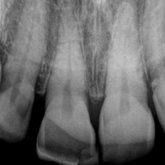

He received his Diploma in Implantology in 2016 from the University of Pretoria, which he passed with Distinction. He is also a member of the International Team for Implantology (ITI), which is based in Switzerland and offers members access to the latest research and cutting-edge techniques.